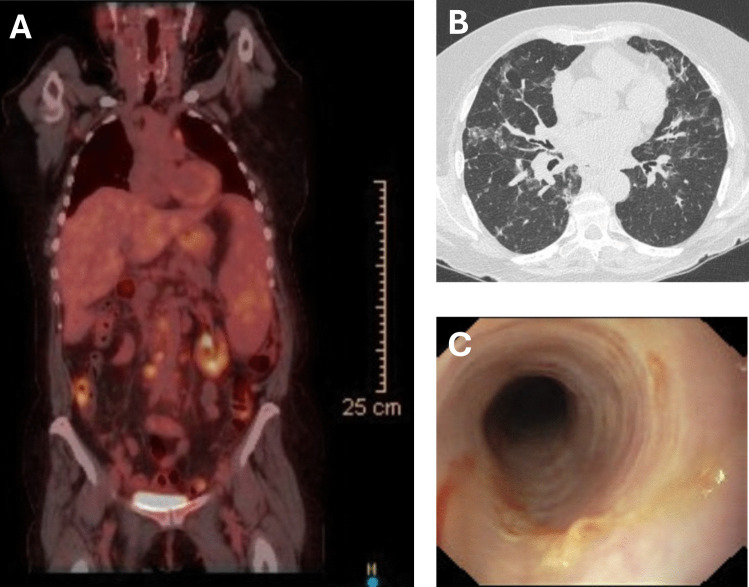

磷酸肌肽3-激酶(PI3Ks),特别是PI3Kδ通路,在调节免疫功能中起着至关重要的作用。该通路的改变,无论是过度激活,如活化PI3Kδ综合征(APDS),还是很少被描述的低激活,都会深刻影响免疫功能,并与一系列免疫缺陷和自身免疫性疾病有关。本报告描述了两例与PI3Kδ通路失调相关的迟发性免疫缺陷,每个病例都有独特的突变和临床表现。第一个病例涉及PI3KR1杂合突变(c.5A > T, p.Tyr2Phe),表明PI3Kδ过度激活,西罗莫司有效地控制了这一突变。第二个病例的特征是PIK3CD纯合突变(c.2608C > T, p.Arg870Ter),提示PI3Kδ低激活,临床特征包括银屑病关节炎和溃疡性结肠炎。这些病例强调了异质性的临床特征和管理这种罕见的遗传变异的挑战。这些病例强调了在表现出传染性和非传染性自身免疫或免疫失调并发症迹象的个体中考虑原发性免疫缺陷的重要性。及时的基因筛查和战略性治疗方法对于有效管理这些疾病和减轻与免疫抑制治疗相关的风险至关重要。这些见解强调需要更深入地了解免疫缺陷的遗传因素,以设计个性化的治疗策略,从而大大提高患者的生活质量。

Phosphoinositide 3-kinases (PI3Ks), particularly the PI3Kδ pathway, play a crucial role in regulating immune functions. Alterations in this pathway, either as hyperactivation, such as in activated PI3Kδ syndrome (APDS), or rarely described hypoactivation, profoundly influence immune function and are linked to a spectrum of immunodeficiencies and autoimmune conditions. This report describes two cases of late-onset immunodeficiencies associated with PI3Kδ pathway dysregulation, each presenting with unique mutations and clinical manifestations. The first case involves a heterozygous mutation in PI3KR1 (c.5A > T, p.Tyr2Phe) indicative of PI3Kδ hyperactivation, effectively managed with sirolimus. The second case is characterized by a homozygous mutation in PIK3CD (c.2608C > T, p.Arg870Ter), suggesting PI3Kδ hypoactivation, with clinical features including psoriatic arthritis and ulcerative colitis. These cases underscore the heterogeneous clinical features and the challenges in managing such rare genetic variants. These cases underscore the importance of considering primary immunodeficiency in individuals exhibiting signs of both infectious and non-infectious autoimmune or immune dysregulation complications. Prompt genetic screening and strategic therapeutic approaches are crucial for effectively managing these conditions and mitigating the risks associated with immunosuppressive treatments. These insights emphasize the need for a deeper understanding of genetic factors in immunodeficiencies to devise personalized treatment strategies that substantially improve patients' quality of life.